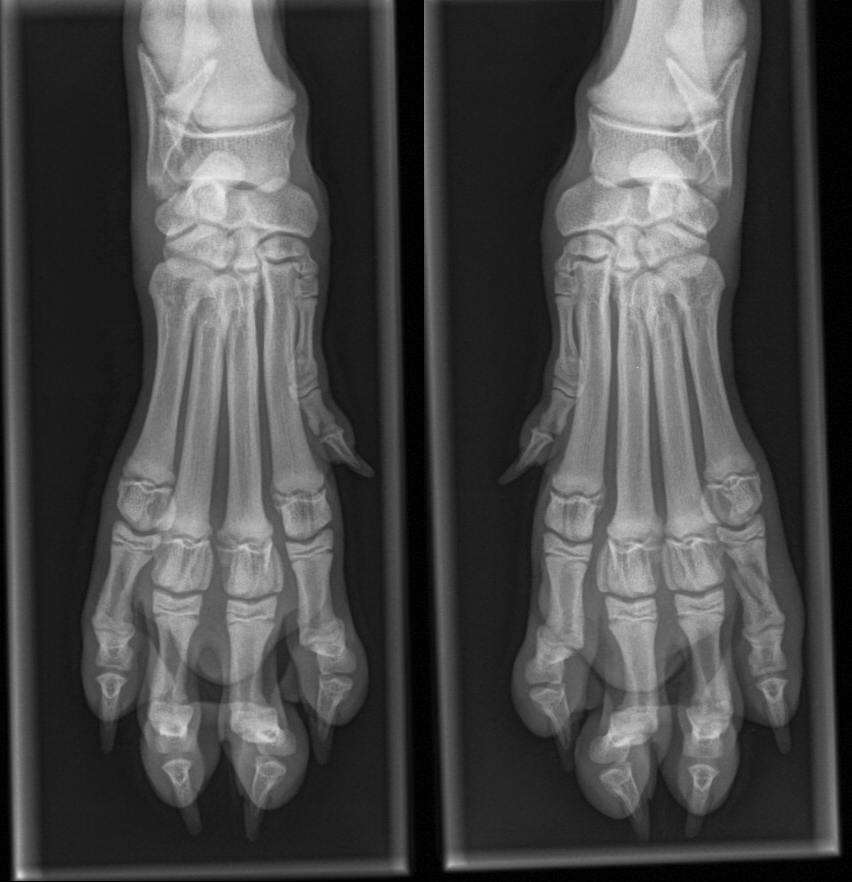

Vad är diagnosen?